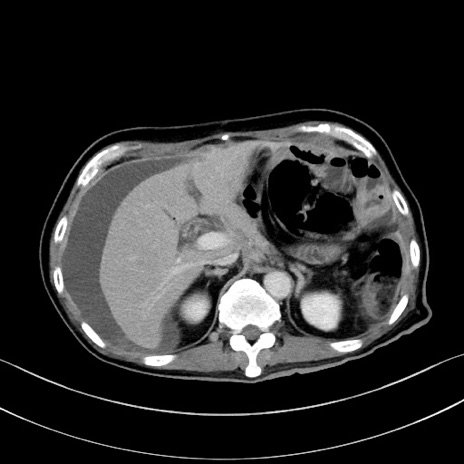

冠状断像

【症例】60歳代男性

【主訴】嘔吐

【現病歴】胃癌にて胃全摘後。食思不振が悪化し、夜中に嘔吐することがある。

【既往歴】胃癌、胃全摘、脾摘、胆摘後

【データ】WBC 5900、CRP 10.56